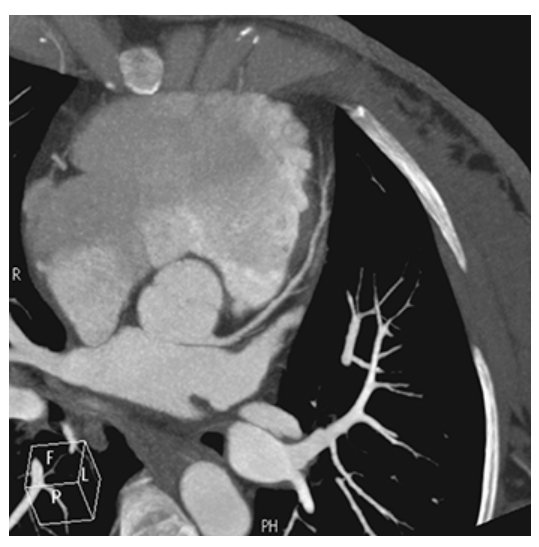

Coronary Artery Disease. Maximum intensity projection CT coronary angiogram showing near-complete occlusion of the right coronary artery.